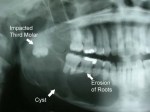

Impacted Teeth. Wisdom teeth, or else called third molars, are the last collection of teeth to establish. Impacted wisdom teeth can lead to swelling, discomfort, and infection of the periodontal cells bordering the knowledge teeth. Furthermore, impacted wisdom teeth could cause long-term damage to nearby teeth, gum tissues, and bone and can sometimes cause the formation of cysts or tumors that could damage areas of the jaw.

It’s not merely wisdom teeth that in some cases become affected and require to be eliminated. Other teeth, such as the cuspids and the bicuspid could become affected and can create the exact same sorts of issues explained with impacted knowledge teeth. An affected tooth is one that falls short to appear into the orthodontic arch within the specific time. Given that impacted teeth do not erupt, they are kept throughout the individual’s lifetime unless removed or exposed surgically. Pearly whites may come to be impacted due to adjacent teeth, dense overlying bone, too much soft cells or a hereditary problem. Many commonly, the source of impacting is inadequate arc length and space through which to emerge. That is the complete length of the alveolar arc is smaller sized than the tooth arch (the combined mesiodistal width of each tooth). Considering that they are the last teeth to appear in the oral dental caries, the 3rd molars are regularly affected. Mandibular third molars are a lot more typically affected than their maxillary counterparts. As a basic policy, all influenced teeth need to be eliminated unless or else contraindicated. [1]